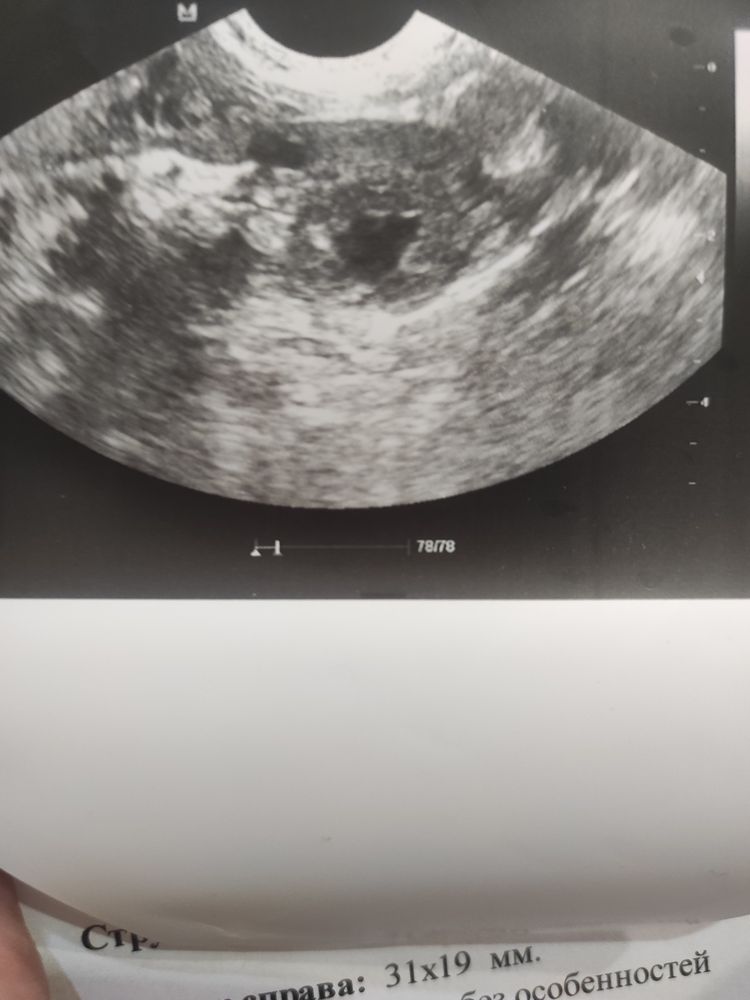

Девочки, помогите пожалуйста, делала УЗИ на 14 ДЦ был доминантый фолликул, 20мм, врач сказал пройти УЗИ на 21 ДЦ, я пошла в другую клинику, тк живу в другом городе, сделали УЗИ , сдувшийся фолликул,, жидкость в малом тазу есть, а вот жёлтого тела нету ((( я у неё спрашиваю а где же жёлтое тело, на что она мне сказала кисты?? Их быть не должно, если киста типо есть, значит овуляции не было((( я не понимаю, всегда читала что после овуляции есть жёлтое тело и это норма. Значит у меня овуляции не было? Я не понимаю (((